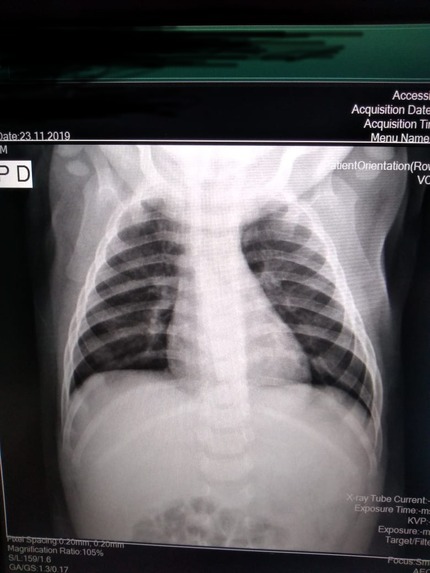

Demanda: Estudo de Caso Clínico (qual o meio de obte-lo: contrato NDA, orçamento?) das análises que fizemos (em anexo) de raio x e tomografia computadorizada obtidos em base pública realizado sob plataforma pública de deep learning com modelo abastecido por datasets públicos de pacientes suspeitos de contágio com covid-19 e outras doenças respiratórias****.

3 - Treinar o Modelo Mellieri Human de Rede Neural Convolucional para detectar o COVID-19 e outras doenças respiratórias em imagens de raios-X e tomografia computadorizada.

4 - Notamos que um paciente pode ter um misto de complicações respiratórias (Covid e Pneumonia por exemplo).

Qual impacto disto nas pesquisas e soluções para combate ao covid-19 como vacinas em função do estágio da doença a exemplo do metadados anexos já que os diagnósticos podem ser únicos para cada paciente no tempo?